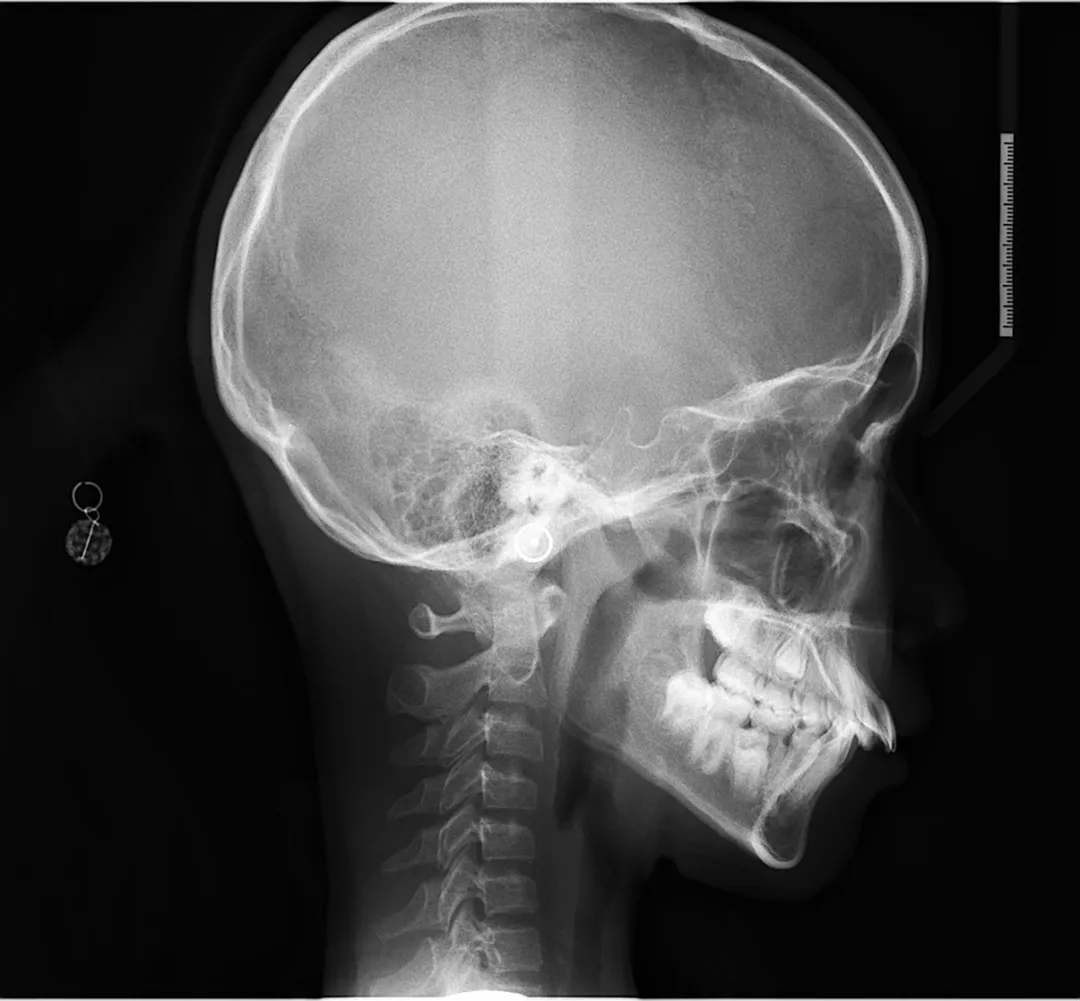

由于骨性Ⅱ类下颌后缩的病例,生长方向是顺时针的,上颌前突、下颌后缩,因此,我们需要给逆时针生长控制,头帽肌激动器能有效地和无托槽隐形牙套配合使用。

另外要控制好垂直高度,在高角骨性II类下颌后缩案例中,不仅可以预防开颌的发生,对面型的改善效果也起到至关重要的作用。

因为如果在牙齿矫正过程中垂直高度显著增加,意味着其下颌发生了顺时针旋转,这时颏前点后移,面部突度会较矫正前加大,这样的治疗对面型的改善几乎没有帮助,甚至可能使侧貌外形恶化。

因此如果替牙期孩子是高角上颌前突(伴随露龈笑)、下颌后缩问题,可以考虑戴头帽肌激动器,对上颌骨产生一个向上向后的力量,同时在采模型的时候让下巴前伸,这样会发生逆时针旋转。